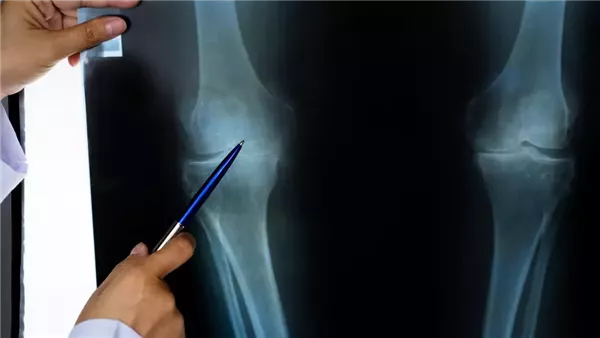

لم تعد آلام الركبة مشكلة مرتبطة بالتقدم في العمر فقط، إذ تكشف دراسات حديثة أن أعدادًا متزايدة من الشباب في الثلاثينيات والأربعينيات أصبحوا يعانون من تلف الركبة، حتى أن بعضهم يضطر إلى إجراء عمليات جراحية مبكرة.

بين عامي 2000 و2017، ارتفعت عمليات استبدال الركبة بنسبة 240% بين الفئة العمرية من 45 إلى 64 عامًا، وفقًا لتقرير وزارة الصحة الأمريكية، ما يعكس حجم الأزمة المتزايدة.

ودراسة نُشرت في مجلة هشاشة العظام والغضاريف أوضحت أن التغيرات البنيوية المبكرة في الركبة شائعة منذ سن الثلاثين، حتى لدى من لا تظهر عليهم أعراض.

وأظهرت الدراسة، التي شارك فيها باحثون من جامعة أولو الفنلندية، أن أكثر من نصف المتطوعين ظهرت لديهم عيوب في الغضروف المفصلي ونتوءات عظمية طفيفة، فيما رُبطت النتائج بشكل رئيسي بارتفاع مؤشر كتلة الجسم.